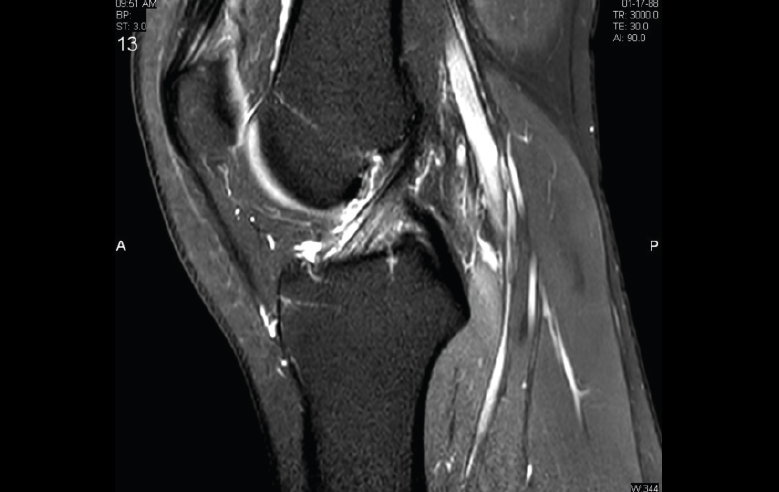

1.2.2. Ligamento cruzado anterior (LCA) (Figuras 40, 41, 42, 43 y 44)

Figura 41. Cortes de secuencia sagital T2 Fat-Sat de resonancia magnética de rodilla: rotura central del ligamento cruzado anterior.

Figura 43. Corte sagital oblicuo T2 de resonancia magnética de rodilla: plastia del ligamento cruzado anterior íntegra.

Figura 44. Corte de secuencia sagital T2 Fat-Sat y T2 de resonancia magnética de rodilla: rotura de plastia del LCA.